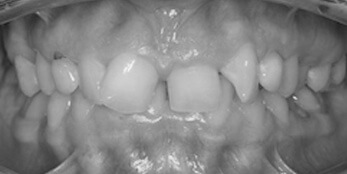

See the smiles we have transformed